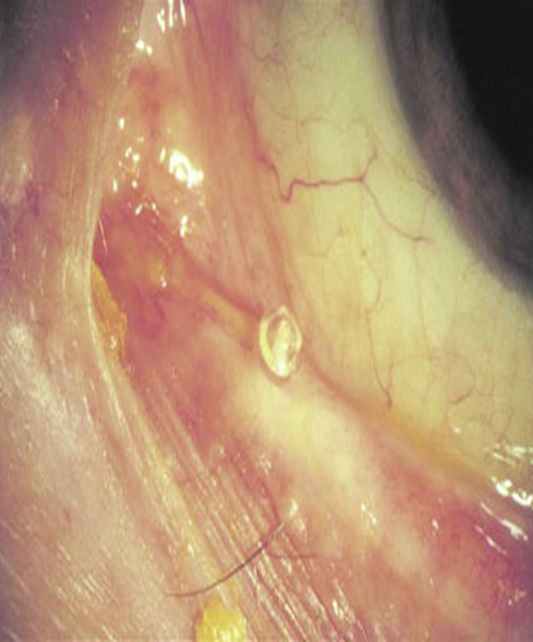

En mi experiencia y opinión personal, sostengo hace largo tiempo que el uso de los denominados tapones lagrimales de silicona pueden agravar los cuadros inmunológicos y/o inflamatorios presentes en el ojo seco, al fomentar los fenómenos inmunocompentes por fricción sobre la superfcie ocular (Figs. 22, 23, 24).

Figura 22: Borde del tapón lagrimal sobre la superficie conjuntival y acúmulos secretorios secundarios.

Figura 23: Borde del tapón deteriorado friccionando la superficie ocular. Secreción, congestión y edema conjuntival.

Figura 24: Contacto del tapón lagrimal en conjuntiva.

Sostuve y sostengo también, que esa fricción crónica puede estimular a los linfocitos conjuntivales y en pacientes susceptibles desencadenar fenómenos de tipo linfoides.